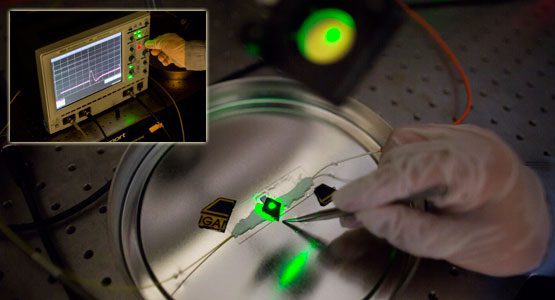

‘Sister cell’ profiling aims to shut down cancer metastasis

Michigan engineers release individual cells from a specially-designed chip using laser pulses.